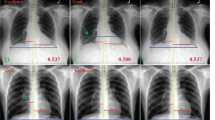

Although a novel deep learning software was proposed using post-processed images obtained by the fusion between X-ray images of normal post-operative radiography and surgical sponge, the association of the retained surgical item detectability with human visual evaluation has not been sufficiently examined. In this study, we investigated the association of retained surgical item detectability between deep learning and human subjective evaluation.

A deep learning model was constructed from 2987 training images and 1298 validation images, which were obtained from post-processing of the image fusion between X-ray images of normal post-operative radiography and surgical sponge. Then, another 800 images were used, i.e., 400 with and 400 without surgical sponge. The detection characteristics of retained sponges between the model and a general observer with 10-year clinical experience were analyzed using the receiver operator characteristics.

The following values from the deep learning model and observer were, respectively, derived: Cutoff values of probability were 0.37 and 0.45; areas under the curves were 0.87 and 0.76; sensitivity values were 85% and 61%; and specificity values were 73% and 92%.

For the detection of surgical sponges, we concluded that the deep learning model has higher sensitivity, while the human observer has higher specificity. These characteristics indicate that the deep learning system that is complementary to humans could support the clinical workflow in operation rooms for prevention of retained surgical items.